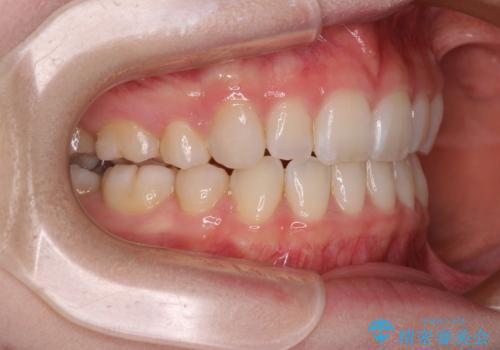

4本の歯を抜歯したことで、飛び出していた口元が引っ込み、横顔が大きく改善されました。

- 前歯の出っ歯と口元の閉じにくさを気にして来院された患者様です。

口元を積極的に引っ込めるために、上下左右の小臼歯4本を抜歯することとしました。